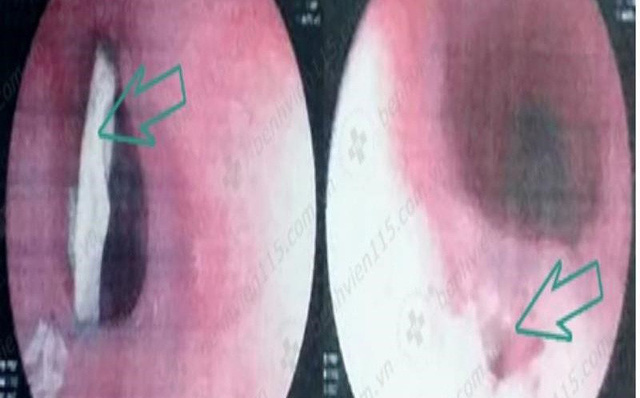

Kết quả nội soi thực quản cho thấy mảnh xương gà (trái) và lỗ thủng thực quản sau khi gắp xương gà ra ngoài (phải). Ảnh: BV CUNG CẤP

Kết quả nội soi thực quản cho thấy xương gà dài khoảng 40 mm nằm ở 1/3 giữa thực quản. Điều đáng nói xương gà nằm ngang, hai đầu cắm sâu vào thành thực quản nên nhiều khả năng gây thủng thành thực quản.

Sau khi lấy xương gà ra ngoài, các bác sĩ (BS) phát hiện thành sau phải thực quản giữa có một vết thủng khoảng 3 mm. Kết quả chụp CT scan cho thấy ông H. bị viêm trung thất .